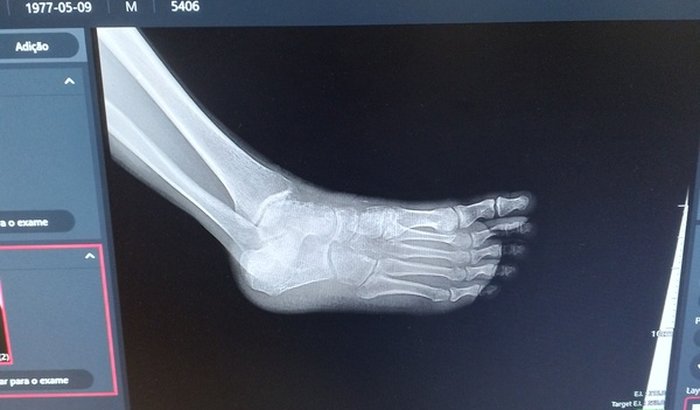

Eu sou isaias criei essa vaquinha pois dia 02 de setembro quebrei o nariz o maquixilar e estourei minha boca toda por dentro tive uma fratura na navicular preciso fazer uma cirurgia e pagar minhas conta  ver tudo

Eu sou isaias criei essa vaquinha pois dia 02 de setembro quebrei o nariz o maquixilar e estourei minha boca toda por dentro tive uma fratura na navicular preciso fazer uma cirurgia e pagar minhas conta